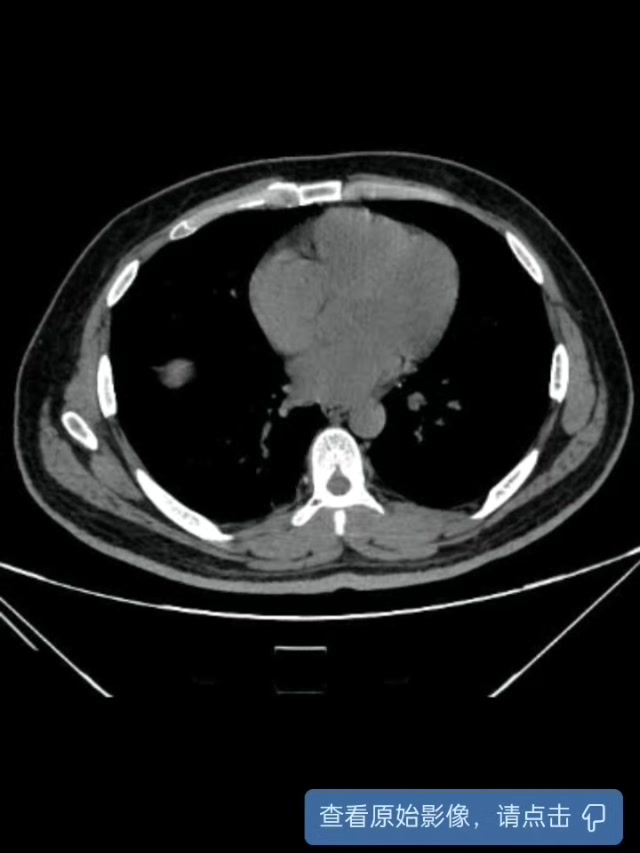

【治疗经过及结果】:第一次入院(10.12)后完善术前必备检查,急诊行经尿道输尿管内支架置入。术后次日复查腹部CT见输尿管内支架未跨过结石,但治疗后患者症状较前减轻,复查血结果提示感染控制。

复查腹部CT: